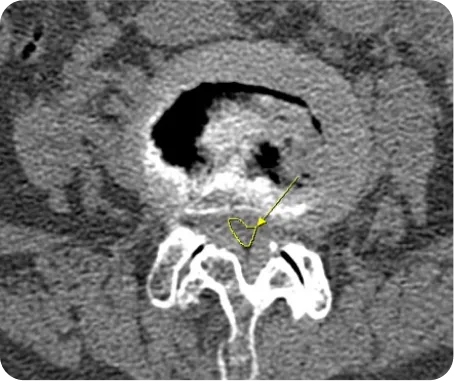

CT *

골절 및 변형의 정확한 양상을 입체적으로 파악 및 골절 이후 뼈의 유합된 정도를 판단

1. 골절 및 변형의 정확한 양상을 입체적으로 파악

2. 골절 이후 뼈의 유합된 정도를 판단

3. 뼈의 여러 방향에서 절단면을 얻을 수 있어서 미세 골절 및 뼈가 겹쳐있는 부위의 골절을 진단

4. 디스크나 협착증 환자의 경우 사고로 인해 악화된 경우 CT로 확인

5. 사고의 충격으로 인한 뇌진탕 여부를 확인

▲ 척추관협착증 환자의 CT